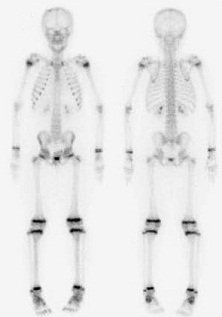

B. Badania obrazowe

- Scyntygrafia kości: Badanie scyntygraficzne pozwala na wykrycie zmian nowotworowych w kościach, nawet przed pojawieniem się zmian na obrazach rentgenowskich.